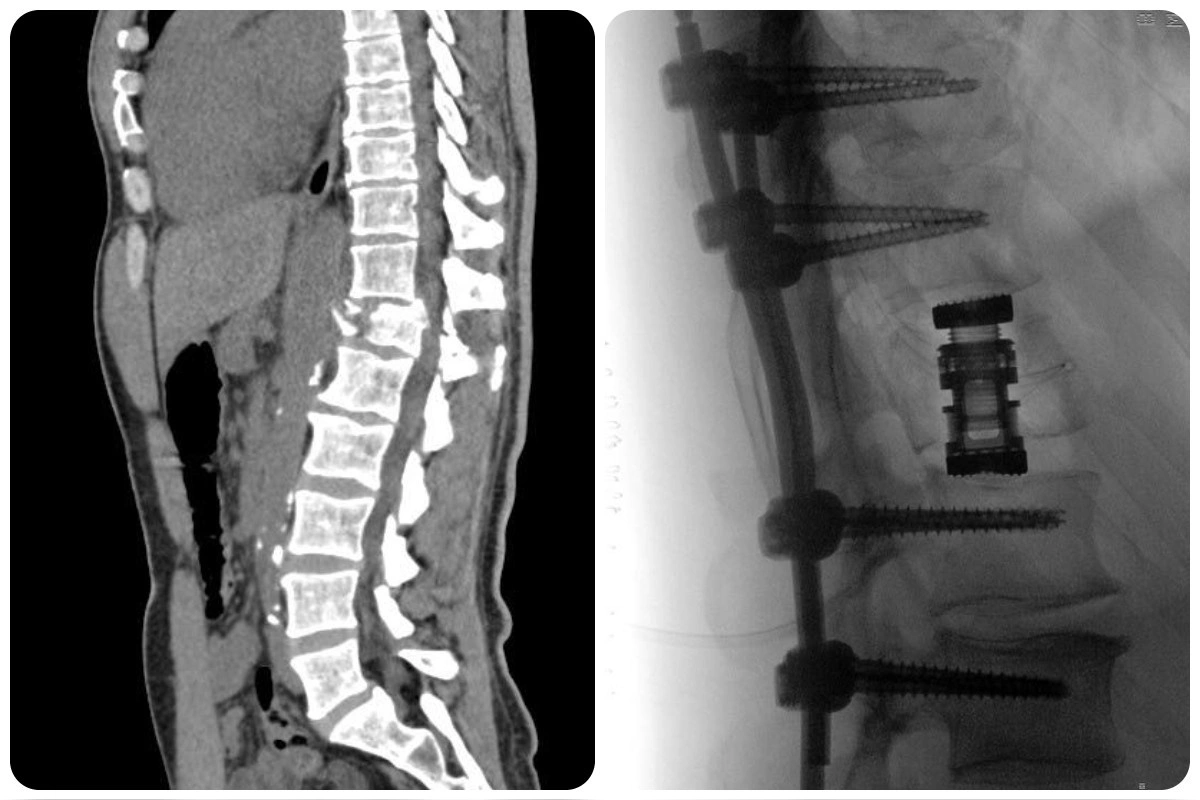

Muž mal závažnú zlomeninu driekového stavca L1 s útlakom nervových štruktúr, čo viedlo k ochrnutiu od pása nadol. Bez rýchleho a odborného zásahu by ostal pripútaný na lôžko. V prvej fáze neurochirurgovia fixovali chrbticu titánovou konštrukciou, čím stabilizovali komplexnú zlomeninu a zároveň dekompresiou uvoľnili utlačené nervy.

Po niekoľkých dňoch nasledovala druhá, kľúčová časť operácie – miniinvazívna MISS retropleurálna korpektómia stavca L1. Tento vysoko špecializovaný zákrok umožnil odstránenie poškodeného stavca a obnovenie stability chrbtice. Miniinvazívny prístup je výrazne šetrnejší, skracuje dobu hojenia a minimalizuje pooperačné komplikácie.